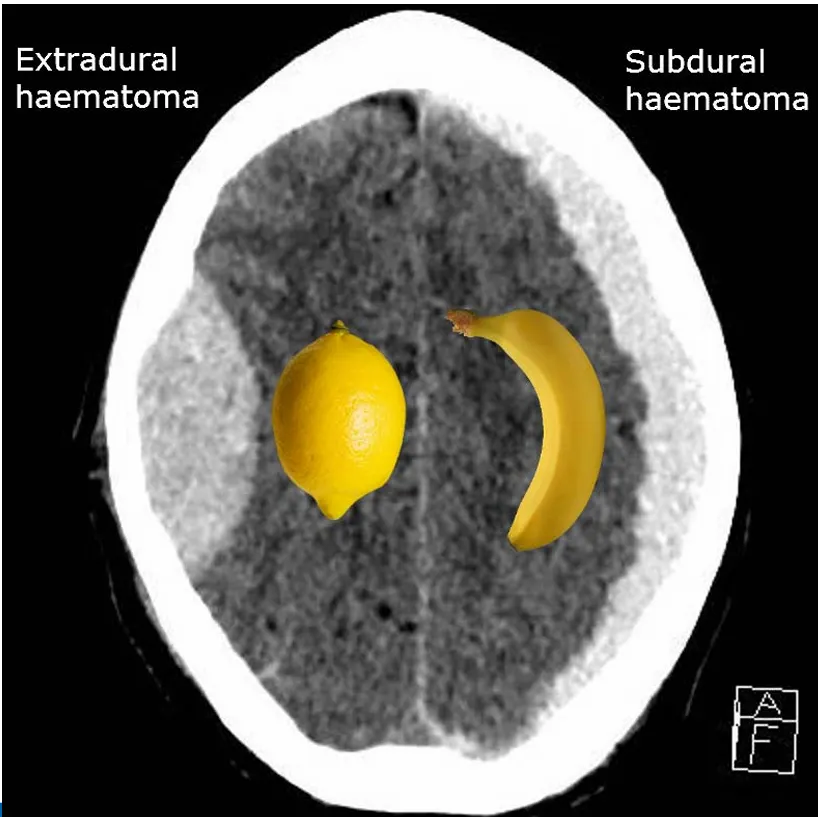

(1) EDH, SDH

(해설) 뇌를 싸고 있는 막을 Dura 라고 하는데, 이것을 기준으로 Dura의 바깥쪽에 생기는 혈종을 EDH, 안쪽에 생기는 혈종을 SDH라고 부릅니다.

그 외에도 뇌 실질 내에 생기는 출혈은 ICH, 거미막 아래에 생긴 출혈은 SAH라고 부릅니다.

(해설) Dura는 좌우반구 사이(interhemispheric fissure)까지 연장되어, 좌측과 우측으로 명확하게 경계가 나뉩니다 따라서 Dura의 아래쪽에 발생하는 SDH는 반대쪽 대뇌반쪽으로 넘어가지 않습니다. 그리고 모양도 초승달 모양처럼 보입니다.

반대로 Dura의 밖에 발생하는 EDH는 midline을 넘어 반대쪽 대뇌반구쪽으로 걸쳐있을 수도 있습니다. 그리고 EDH는 대개 볼록렌즈모양처럼 보입니다.